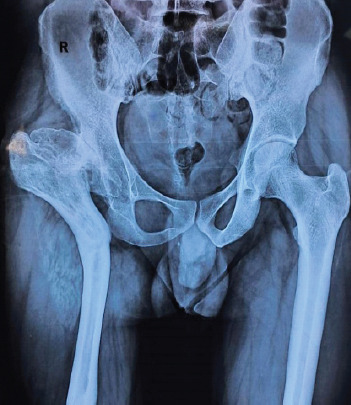

Case report: Here, we discuss the case of a 27-year-old male who had congenital hip dislocation, which was managed conservatively. At 18 years of age, he underwent a pelvic osteotomy and limb lengthening procedure. The symptoms subsided, but there was a recurrence of pain for the past 2 years, which was aggravated with movements. He was diagnosed with Crowe type IV dysplastic hip, and a right total hip with long stem was carried out along with subtrochanteric osteotomy. However, at 3 months of follow-up, the union was not sufficiently appreciated on radiograph, and the patient still complained of pain.